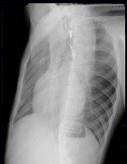

21岁男性患者,劳累后心悸、气促5年,听诊第2肋间有喷射性杂音,胸部三位片如图所示,你认为正确的描述和答案是 ( )A、考虑房间隔缺损B、...

问题 21岁男性患者,劳累后心悸、气促5年,听诊第2肋间有喷射性杂音,胸部三位片如图所示,你认为正确的描述和答案是 ( )

选项 A、考虑房间隔缺损 B、考虑室间隔缺损 C、右前斜位示左心房食管压迹未见明显加深 D、左、右前斜位示右心房段延长 E、后前位示心脏左移,主动脉结缩小,肺动脉段突出

答案 ACDE